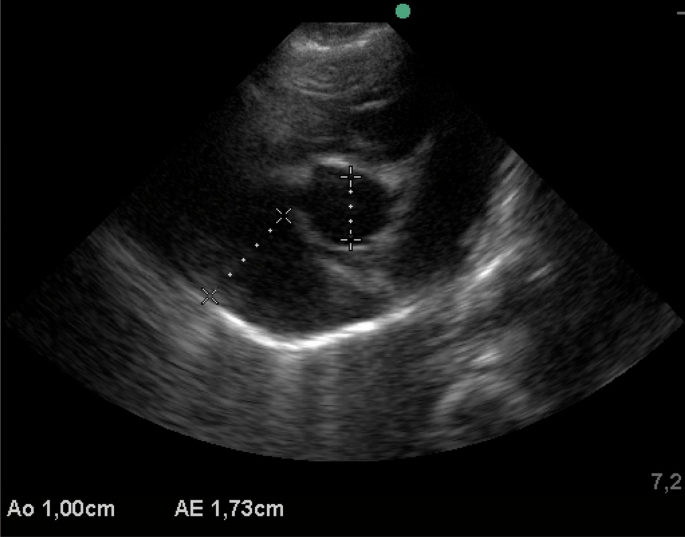

There was a significant difference for the size of the LA, Ao and LA/Ao ratio, which was greater at 90 (LA: 2.30 ± 0.29, LA/Ao: 1.55 ± 0.13) days and 120 (LA: 2.59 ± 0.30, LA/Ao: 1.52 ± 0.16) days of age. Figure 3 shows echocardiographic evaluation, M-mode, left ventricular diameter end-diastolic and end-systolic. EF and LVFS differed during the age periods, with the lowest values at 14 and 30 days of age for both parameters. The size of the LA and diameter of the aorta differed significantly at different time points analysed, with the LA dimension gradually increasing with age. There was also a significant difference in the LA/Ao ratio (1 day: 1.47 ± 0.18, 7 days: 1.40 ± 0.24, 14 days: 1.28 ± 0.18, 21 days: 1.35 ± 0.13—P = 0.0001). There was no difference in the time points analyzed regarding flow and pulmonary velocity and their respective pressure gradients. Figure 4 shows the echocardiographic evaluation, two-dimensional mode, left atrium/aorta ratio.

The echocardiographic examination was obtained with the use of an ultrasound device (M-turbo Sonosite model) with a Doppler function and 2–8 MHz multifrequency sectorial transducer in 2D mode. In diastole, through the right parasternal window, the thickness of the interventricular septum (IVSd), left ventricle internal diameter (LVIDd) and thickness of the left ventricular free wall (LVFWd) were analyzed. In systole, interventricular septum thickness (IVSs), left ventricle internal diameter (LVIDs) and left ventricular free wall thickness (LVFWs) were analyzed. The left ventricular fraction shortening (LVFS), ejection fraction (EF), left atrial diameter (LA) in systole and diastolic aorta (Ao), and left atrium/aorta ratio (LA/Ao) were also compiled, along with pulmonary flow velocity (pul. velocity) and pulmonary pressure gradient (pres. grd.). The following formula was used to calculate LVFS (%): (LVIDd—LVIDs/LVIDd) × 100. It was not possible to attach the electrocardiograph´s cable to perform the echocardiogram, so measurements were taken in systole with the ventricle at its smallest diameter and in diastole with its largest diameter. The left atrium was measured at its greatest diameter at the end of systole. The means were calculated based on three measurements, all taken by the same operator (ASCA).